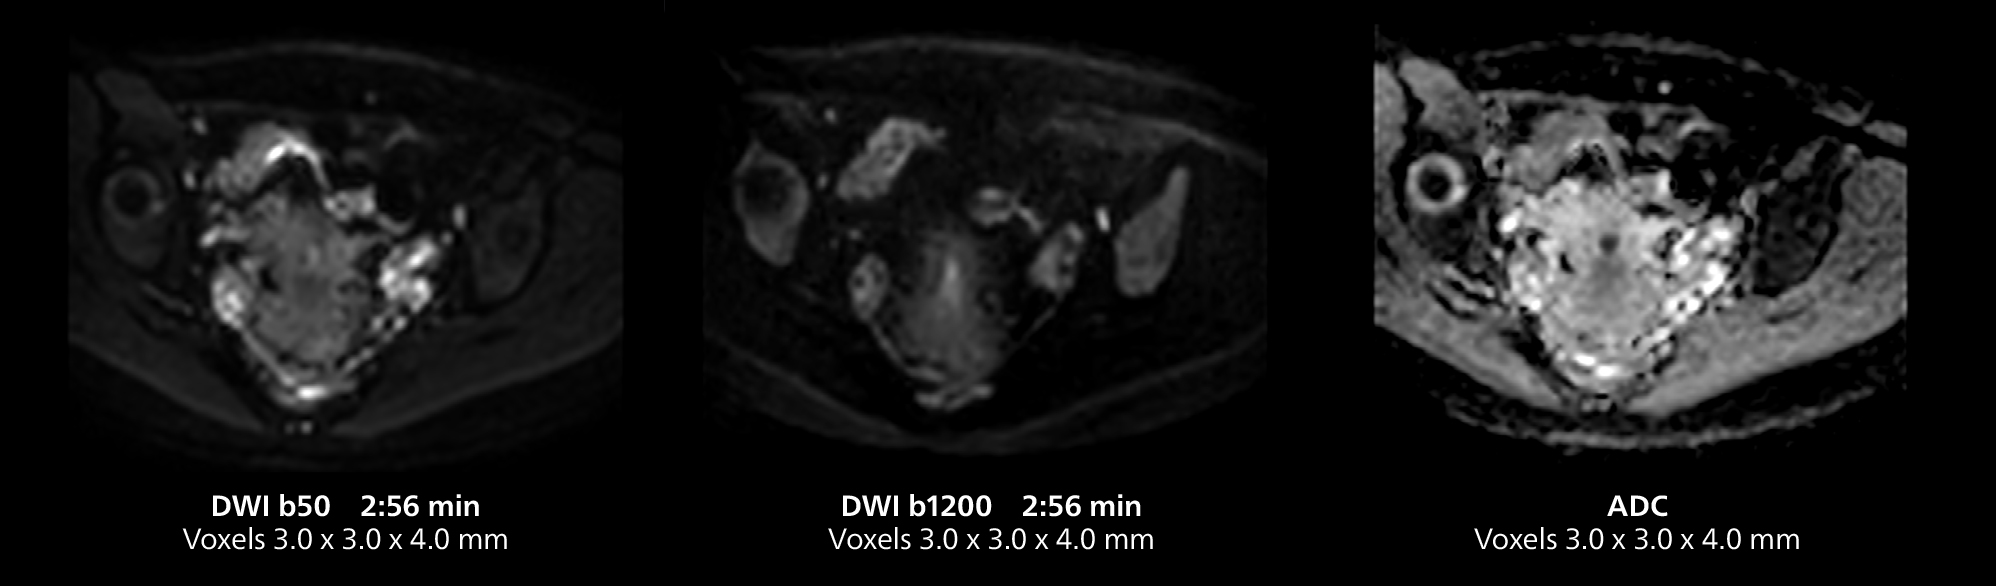

Le Dr Gellée estime que la fiabilité des acquisitions en respiration libre est “la caractéristique qui fait la plus grande différence au quotidien. Les séquences 3D en respiration libre sont très reproductibles et l’acquisition axiale est très bonne. Par exemple, pour l’endométriose, qui est l’un de mes domaines de prédilection, elles offrent un contraste élevé et une bonne résolution, ce qui me permet de voir les moindres détails. Nous utilisons également la respiration libre pour l’imagerie du foie et du pancréas. Dans les examens du foie multiphases, la respiration libre 4D offre une résolution temporelle de 3 secondes, permettant une acquisition dynamique avec plusieurs phases artérielles.”

Cet exemple comprend une IRM 3D en respiration libre et une IRM dynamique 4D en respiration libre d’un foie métastasé. Une séquence FatSat de haute qualité avec une bonne résolution est produite en 1 min et 36 s avec MultiVane XD pondéré en T2.

Cet exemple d’IRM illustre une bonne résolution et une bonne qualité d’image obtenue avec des temps d’acquisition raisonnables à l’aide du système MR 5300 1.5T avec l’antenne antérieure TorsoCardiac qui permet d’utiliser un champ d’acquisition étendu.